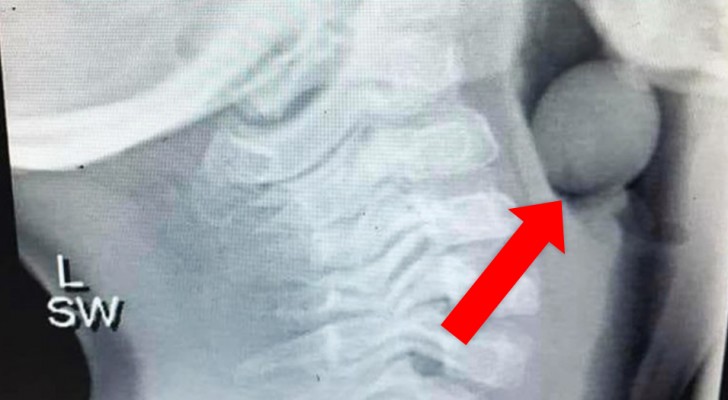

Questa lastra mostra come un chicco d'uva non tagliato può ostruire le vie respiratorie dei più piccoli

La foto in questione è un'immagine a raggi X che mostra chiaramente il chicco d'uva rimasto incastrato nella gola del figlio di 5 anni; fortunatamente le vie respiratorie non erano state del tutto ostruite, e ciò ha permesso al bimbo di sottoporsi ad un intervento per rimuovere l'ostruzione, salvandosi.